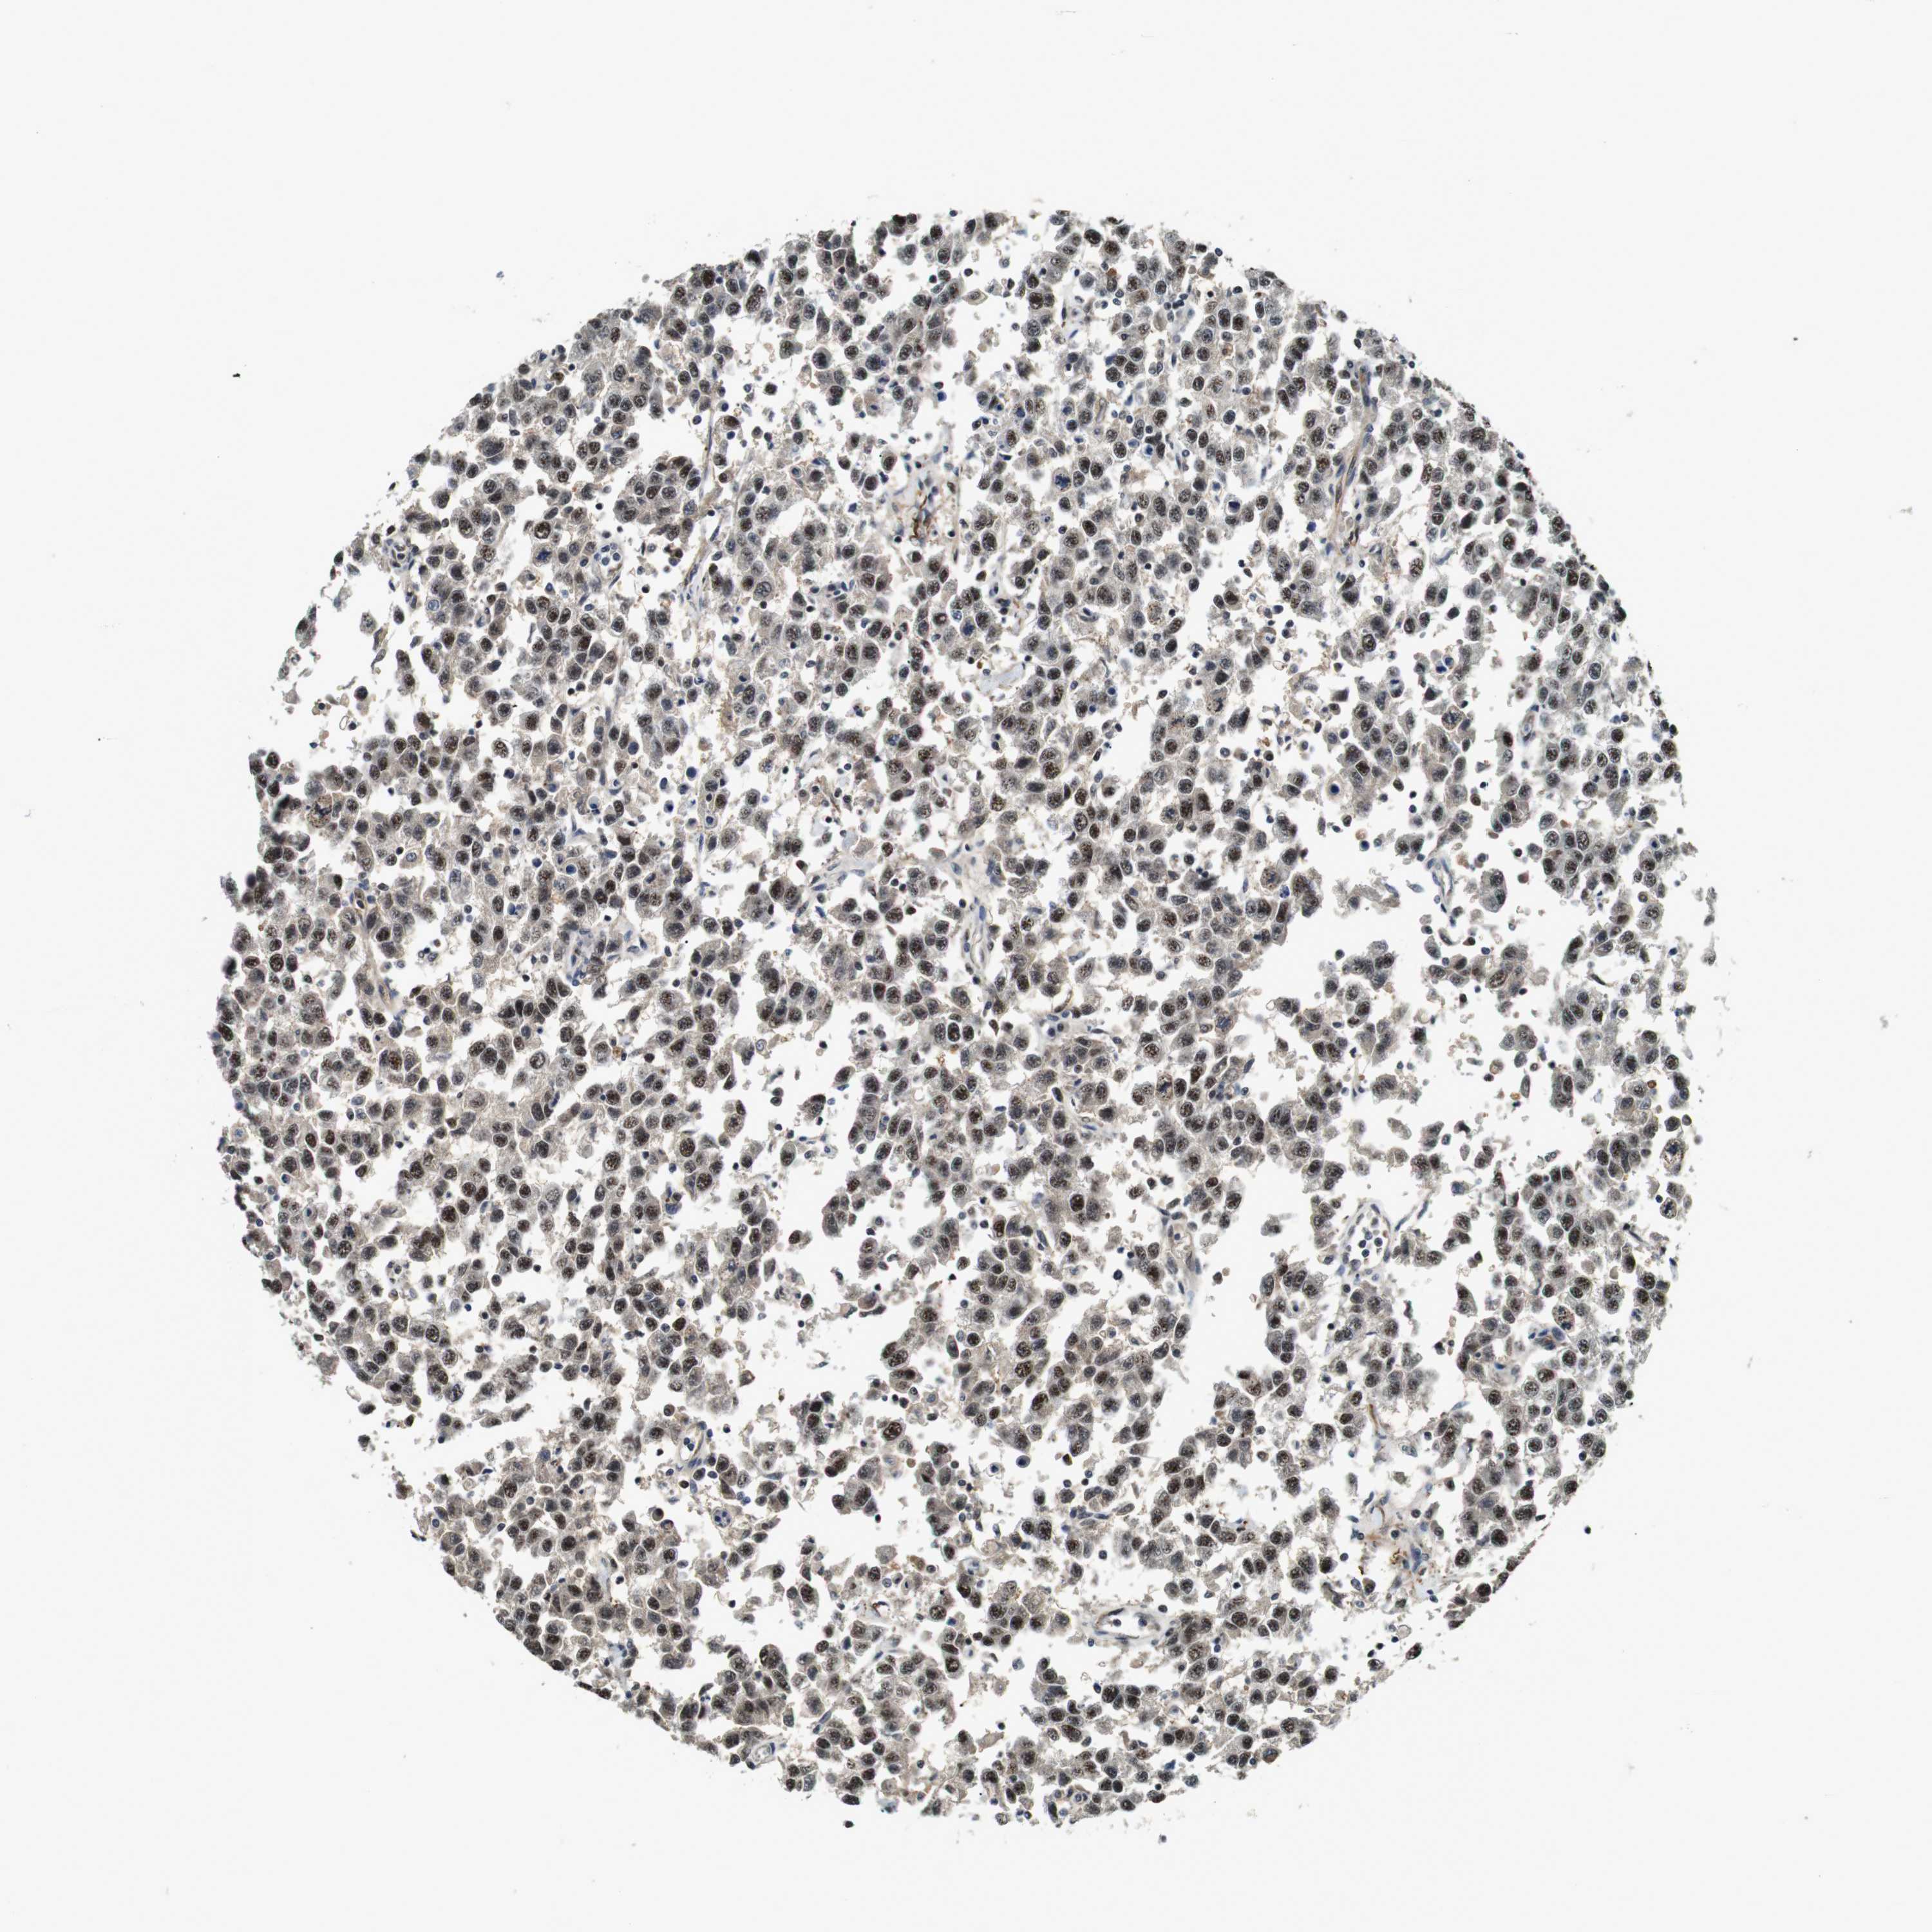

TESTIS CANCER - Protein expressioni

A mouse-over function shows sample information and annotation data. Click on an image to view it in a full screen mode. Samples can be filtered based on level of antibody staining by selecting one or several of the following categories: high, medium, low and not detected. The assay and annotation is described here.

Note that samples used for immunohistochemistry by the Human Protein Atlas do not correspond to samples in the TCGA dataset.

Antibody stainingi

Antibody staining in the annotated cell types in the current human tissue is reported as not detected, low, medium, or high, based on conventional immunohistochemistry profiling in selected tissues. This score is based on the combination of the staining intensity and fraction of stained cells.

Each image is clickable and will lead to virtual microscopy that enables deeper exploration of all samples and also displays staining intensity scores, fraction scores and subcellular localization as well as patient and tissue information for each sample.

Antibody HPA014179

Antibody CAB025128

Staining

High

Medium

Low

Not detected

Intensity

Strong

Moderate

Weak

Negative

Quantity

>75%

75%-25%

<25%

None

Location

Nuclear

Cytoplasmic/membranous

Cytoplasmic/membranous,nuclear

Carcinoma, Embryonal, NOS

Seminoma, NOS